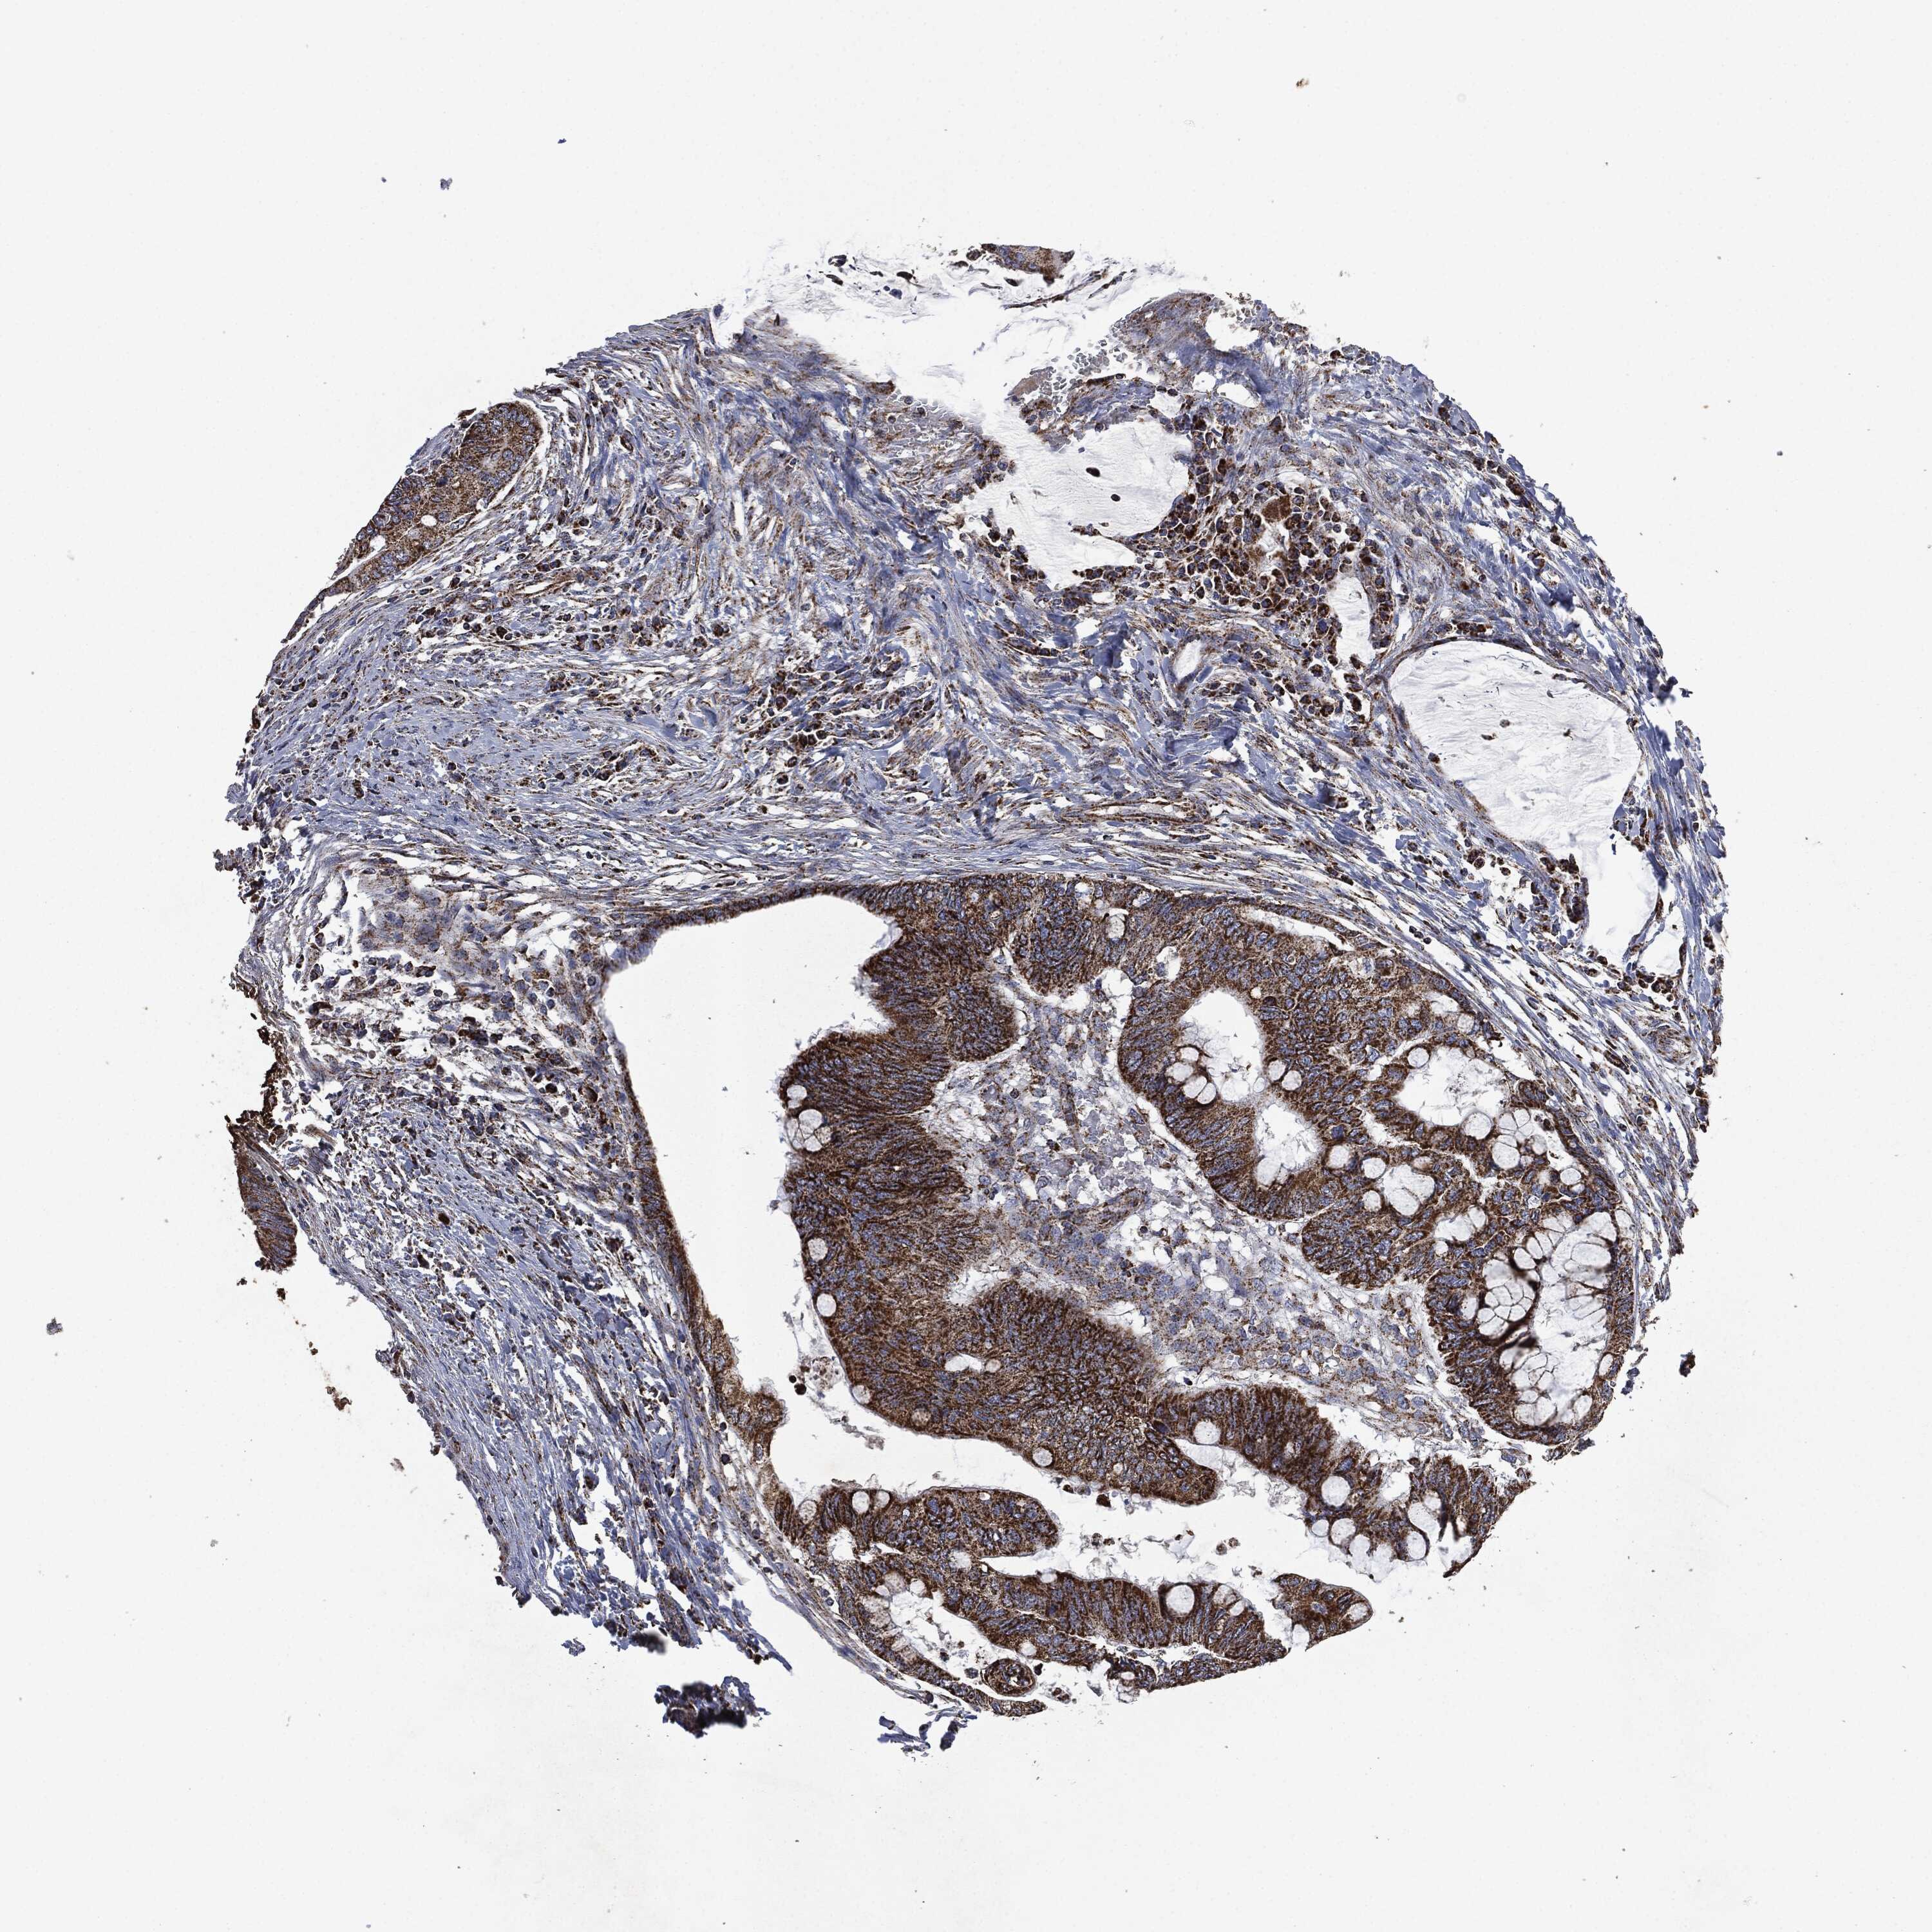

CANCER COLORECTAL CANCER Show tissue menu

COAD TCGA COAD VALIDATION READ TCGA READ VALIDATION PROTEIN COAD CPTAC PROTEIN EXPRESSION

ANTIBODIES

AND

VALIDATION